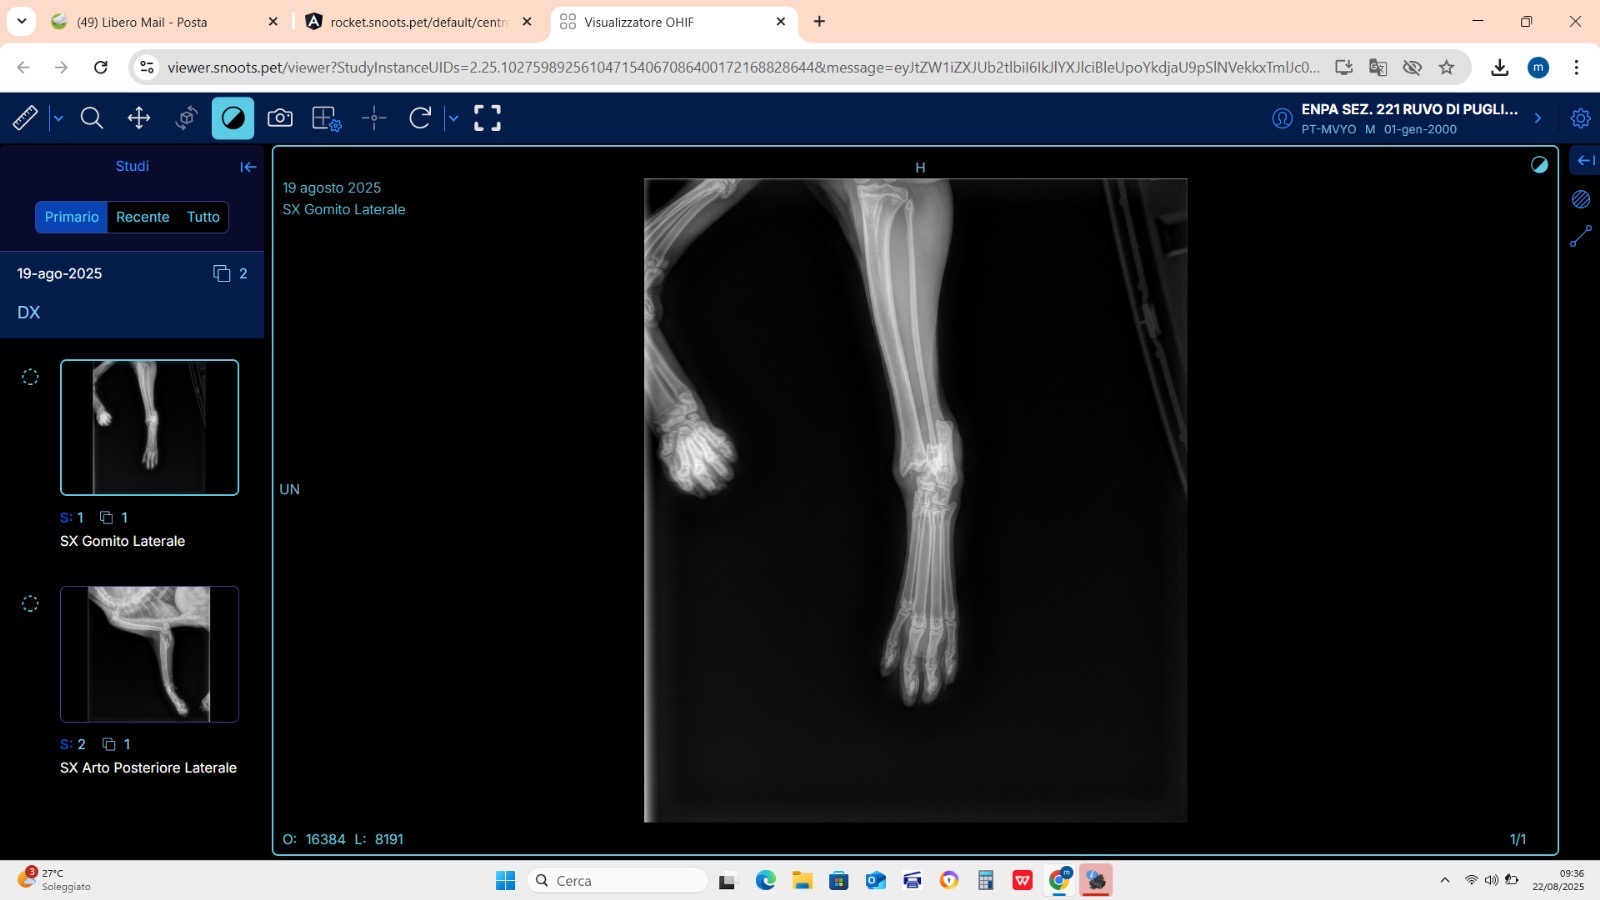

Dopo le prime cure con antibiotici e antinfiammatori, sono stati effettuati esami più approfonditi. Purtroppo i raggi hanno rivelato la presenza di fratture complesse sia alla zampa anteriore che a quella posteriore sinistra. Si tratta di lesioni scomposte e difficili da trattare, che richiedono un intervento ortopedico molto delicato.